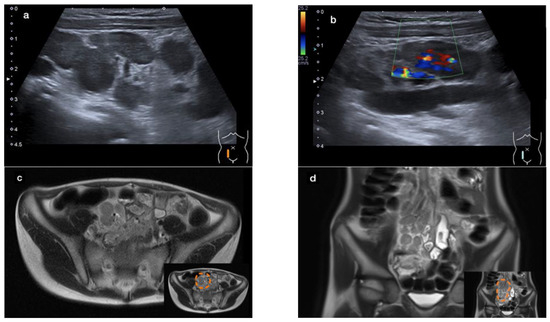

An abdominal ultrasound revealed a large conglomerate of lymph nodes in the right lower abdomen and enteritic bowel loops (Figure 1a). The increased blood circulation within the lymph nodes was visualized by Doppler ultrasound (Figure 1b). The appendix was not visible. Subsequent magnetic resonance imaging (MRI) of the lower abdomen showed a significant thickening of the intestinal wall in the terminal ileum and the ileocecal transition, indicative of terminal ileitis together with remarkably extensive abdominal lymphadenopathy, with the appendix appearing normal (Figure 1c–f).

Figure 1.

Sonographic imaging of a large conglomerate of lymph nodes with increased blood flow shown by a Color Doppler ultrasound in the right lower abdomen (a,b). MRI showing extensive lymphadenopathy in the right lower and middle abdomen (c,d) and the thickened, diffusion-impaired terminal ileum (e,f), as highlighted within the orange dashed line in the lower right corner of the images (case 1).